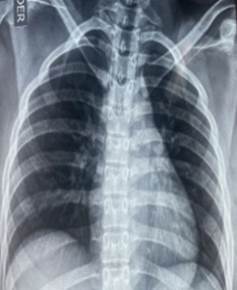

Al tratarse de un cuadro de inicio súbito con alto riesgo de complicaciones se procedió inmediatamente a descartar patologías cardiopulmonares con riesgo vital ante un síndrome respiratorio inespecífico con cianosis central sin repercusión hemodinámica, obteniéndose radiografía de tórax y electrocardiograma no patológico además de un dimero D y troponinas negativas descartándose probable TEP y SCA, con hemoglobina y hematocrito dentro de valores normales, manteniéndose hasta ese entonces sin trastornos de perfusión y clínicamente estable a la hora de su llegada pero la coloración azulada de tegumentos y mucosas persistía a pesar de oxigenoterapia con pulsioximetria de 100%, por lo que se procedió buscar trastornos de la hemoglobina como causa de su cianosis entre ellas carboxihemoglobina, sulfohemoglobina y metahemoglobina siendo incluida en las solicitud de la gasometría la cual al momento de obtener la muestra presento una coloración oscura siendo muy alta la probabilidad de metahemoglobinemia, iniciándose manejo clínico expectante ante su condición estable clínicamente sin criterios para administración del antídoto como es el azul de metileno ante condición clínica estable según guías de manejo de Toxicología. (5)

Ilustración 2 RX DE TÓRAX